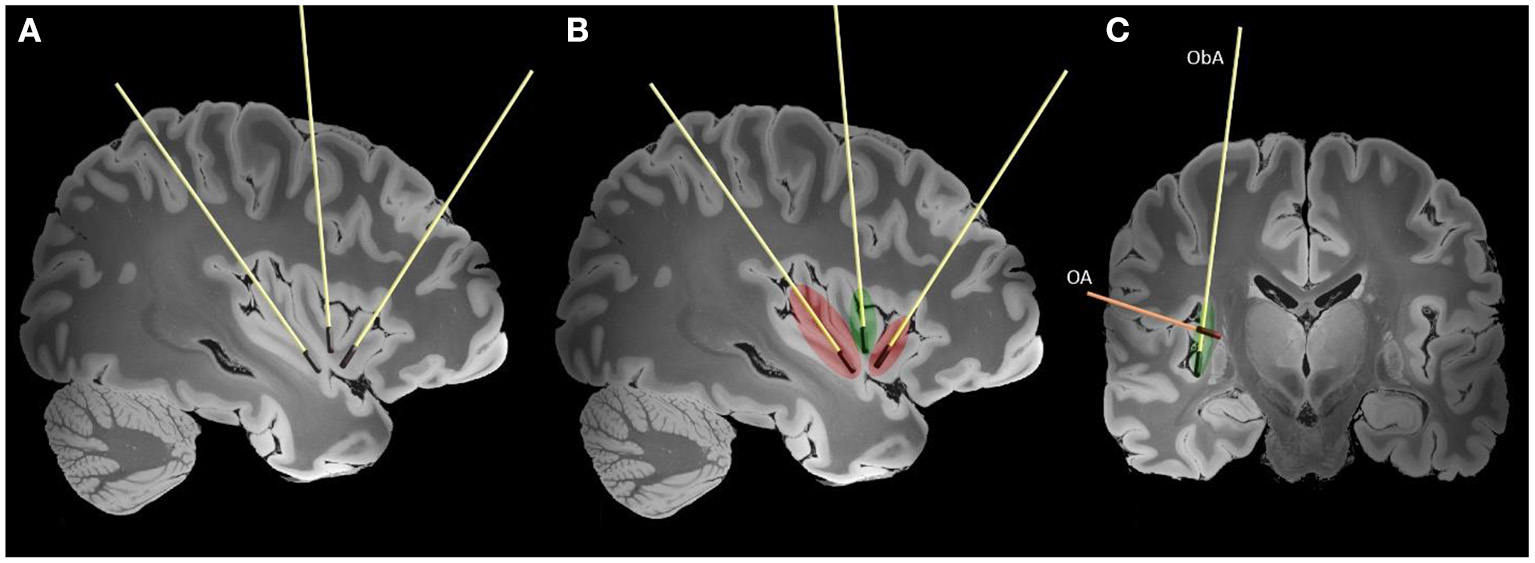

As shown in Figure 3, the main trajectories that have been used for insular LITT were the orthogonal (axially oriented trans-opercular catheters) and parasagittal oblique (anterior and posterior).

Figure 3

Typically used trajectories for the LITT of the insula are shown on high-resolution 7-tesla T1 magnet resonance imaging (MRI) slices of the human brain (38). Laser interstitial therapy trajectories are shown on sagittal (A, B) and coronal (C) slices. The red color represents lesions created by the anterior and posterior laser probes and extent of the disconnection. The green color represents the additional ablation needed to achieve complete insular ablation. In figure the two main LITT trajectories are presented (ObA—oblique parasagittal approach, OA—orthogonal trans-opercular approach).

Several LITT trajectories are available: the orthogonal approach (OA) with the transopercular placement of axially oriented electrodes, and the oblique approach (ObA). While being shorter, the OA approach is potentially more dangerous due to nearby Sylvian vessels. The parasagittal anterior and posterior ObA approaches are potentially safer, but less accurate due to distance to target and bone drilling angle. Another advantage of the ObA approach is higher coverage of the insular surface. The entry point will depend on the chosen trajectory (ObA vs. OA) and should avoid traversing vessels on the surface of the brain, and in the depth of the sulci. While using the oblique trajectory care should be taken to avoid bridging veins. In the coronal plane, the probe is oriented sufficiently close to the surface of the insula to avoid important subcortical white matter tracts. In case of the orthogonal approach a window is chosen between the veins and MCA branches on the insular surface. The entry point should avoid eloquent cortical regions, such as the frontal operculum and rolandic cortex, and allow sufficient coverage of the target by the laser probes. The trajectory and entry point are individually adjusted according to the patients' insular orientation and vascular anatomy. Similar to SEEG, with wider use of robotics (Neuromate, ROSA), the oblique approaches to the insula are becoming more common (43). The full ablation of the insula generally requires three laser probes and is limited by the spatial organization of the insular gyri and sulci (27).

The insula is limited by the anterior, superior, and inferior peri-insular sulci. Morphologically, the insula is divided into two parts by the central insular sulcus: the anterior part consists of 3–5 short gyri, and the posterior portion consisting of 2–3 long gyri. The insula is encompassed and supplied by the M2 segment and associated branches of the middle cerebral artery, and its course should be always considered while planning trajectories (40). Deep to the surface of the insula are white matter tracts associated with movement, language, and cognition (corticospinal tract, fronto-occipital fascicle and superior longitudinal fascicle) (41). The efficient spread of thermal energy in the middle insula is limited by the central sulcus potentially leaving a remnant that might require additional treatment (44). In cases where the lesions are not affecting the full extent of the insula only one two probes might be sufficient. Using only the anterior and posterior probes oriented according to the long and short gyri creates a sufficient ablation that is bordered by the circular sulcus (Figure 3). Additional experiences and understanding of insular connectivity are needed to guide the safe application of LITT for insular lesions.